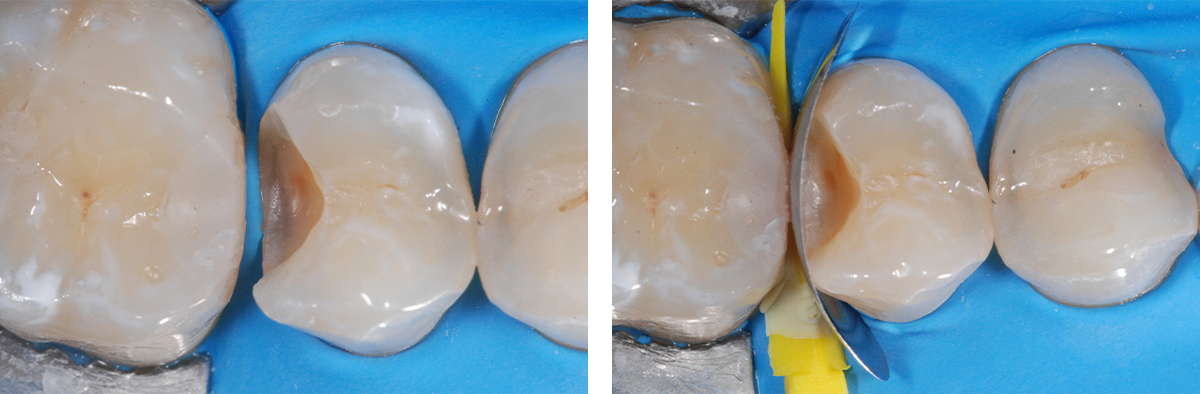

Il sistema QUAD è stato sviluppato in collaborazione con il Dr. Matthew Burton, DDS, ed è il risultato di migliaia di ore di utilizzo clinico e validazione sul campo. Questa sinergia tra visione clinica ed esperienza ingegneristica ha permesso di superare i limiti dei sistemi convenzionali, grazie a un design pratico, intelligente e orientato ai risultati. Elemento chiave del sistema sono gli anelli QUAD asimmetrici, realizzati in nickel-titanio trafilato, capaci di garantire una pressione separatrice costante nel tempo. La speciale punta guida migliora la stabilità del sistema e consente un adattamento estremamente preciso in ogni quadrante, riducendo il rischio di sovracontorni anche nei casi più impegnativi.

La massima efficacia si ottiene grazie alla sinergia tra anello asimmetrico e cunei QUAD a punte separate. Questa combinazione

permette un sigillo cervicale indipendente su entrambi i lati del restauro, favorendo un profilo d’emergenza naturale e la creazione di contatti predicibili, anche in presenza di lesioni profonde, restauri back-to-back o preparazioni multiple. Versatile ed efficiente, QUAD semplifica il flusso di lavoro quotidiano, migliorando la prevedibilità clinica e ottimizzando i tempi operativi.

Quando la complessità aumenta, affidarsi a un sistema progettato per lavorare in modo integrato fa la differenza: QUAD è la risposta evoluta per affrontare con sicurezza i restauri di II classe più complessi.